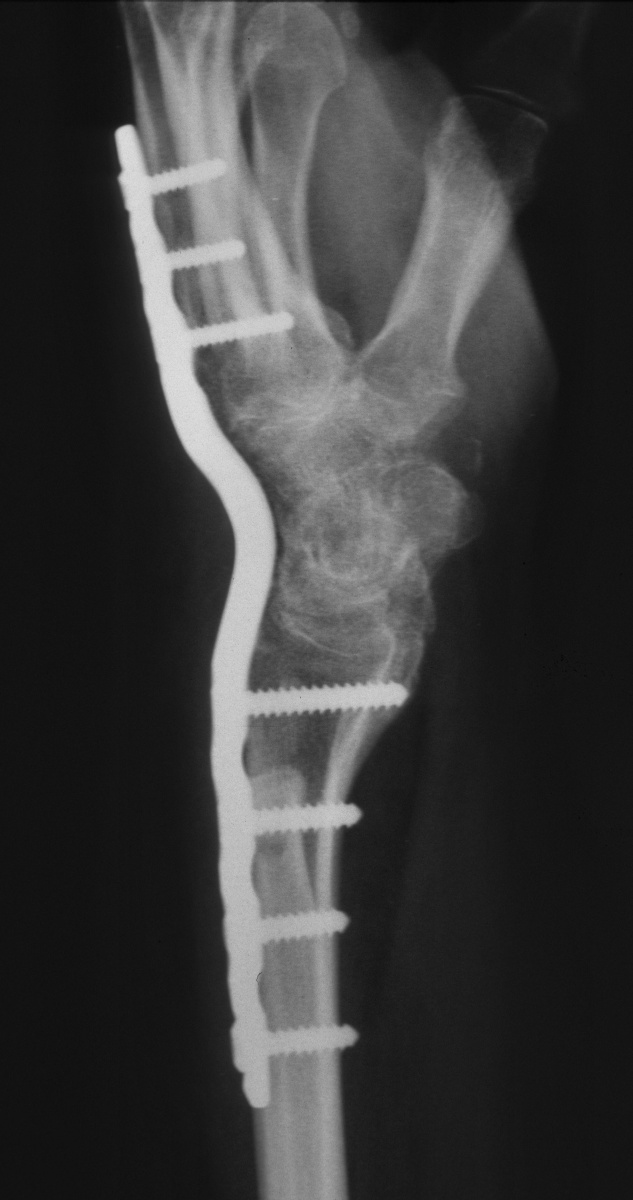

| Eventually, she was treated with wrist fusion, distal ulnar resection and extensor carpi ulnaris tenodesis, and basal joint excision arthroplasty with split abductor pollicis longus anchovie interposition and ligament reconstruction - all through a single dorsal approach.: |